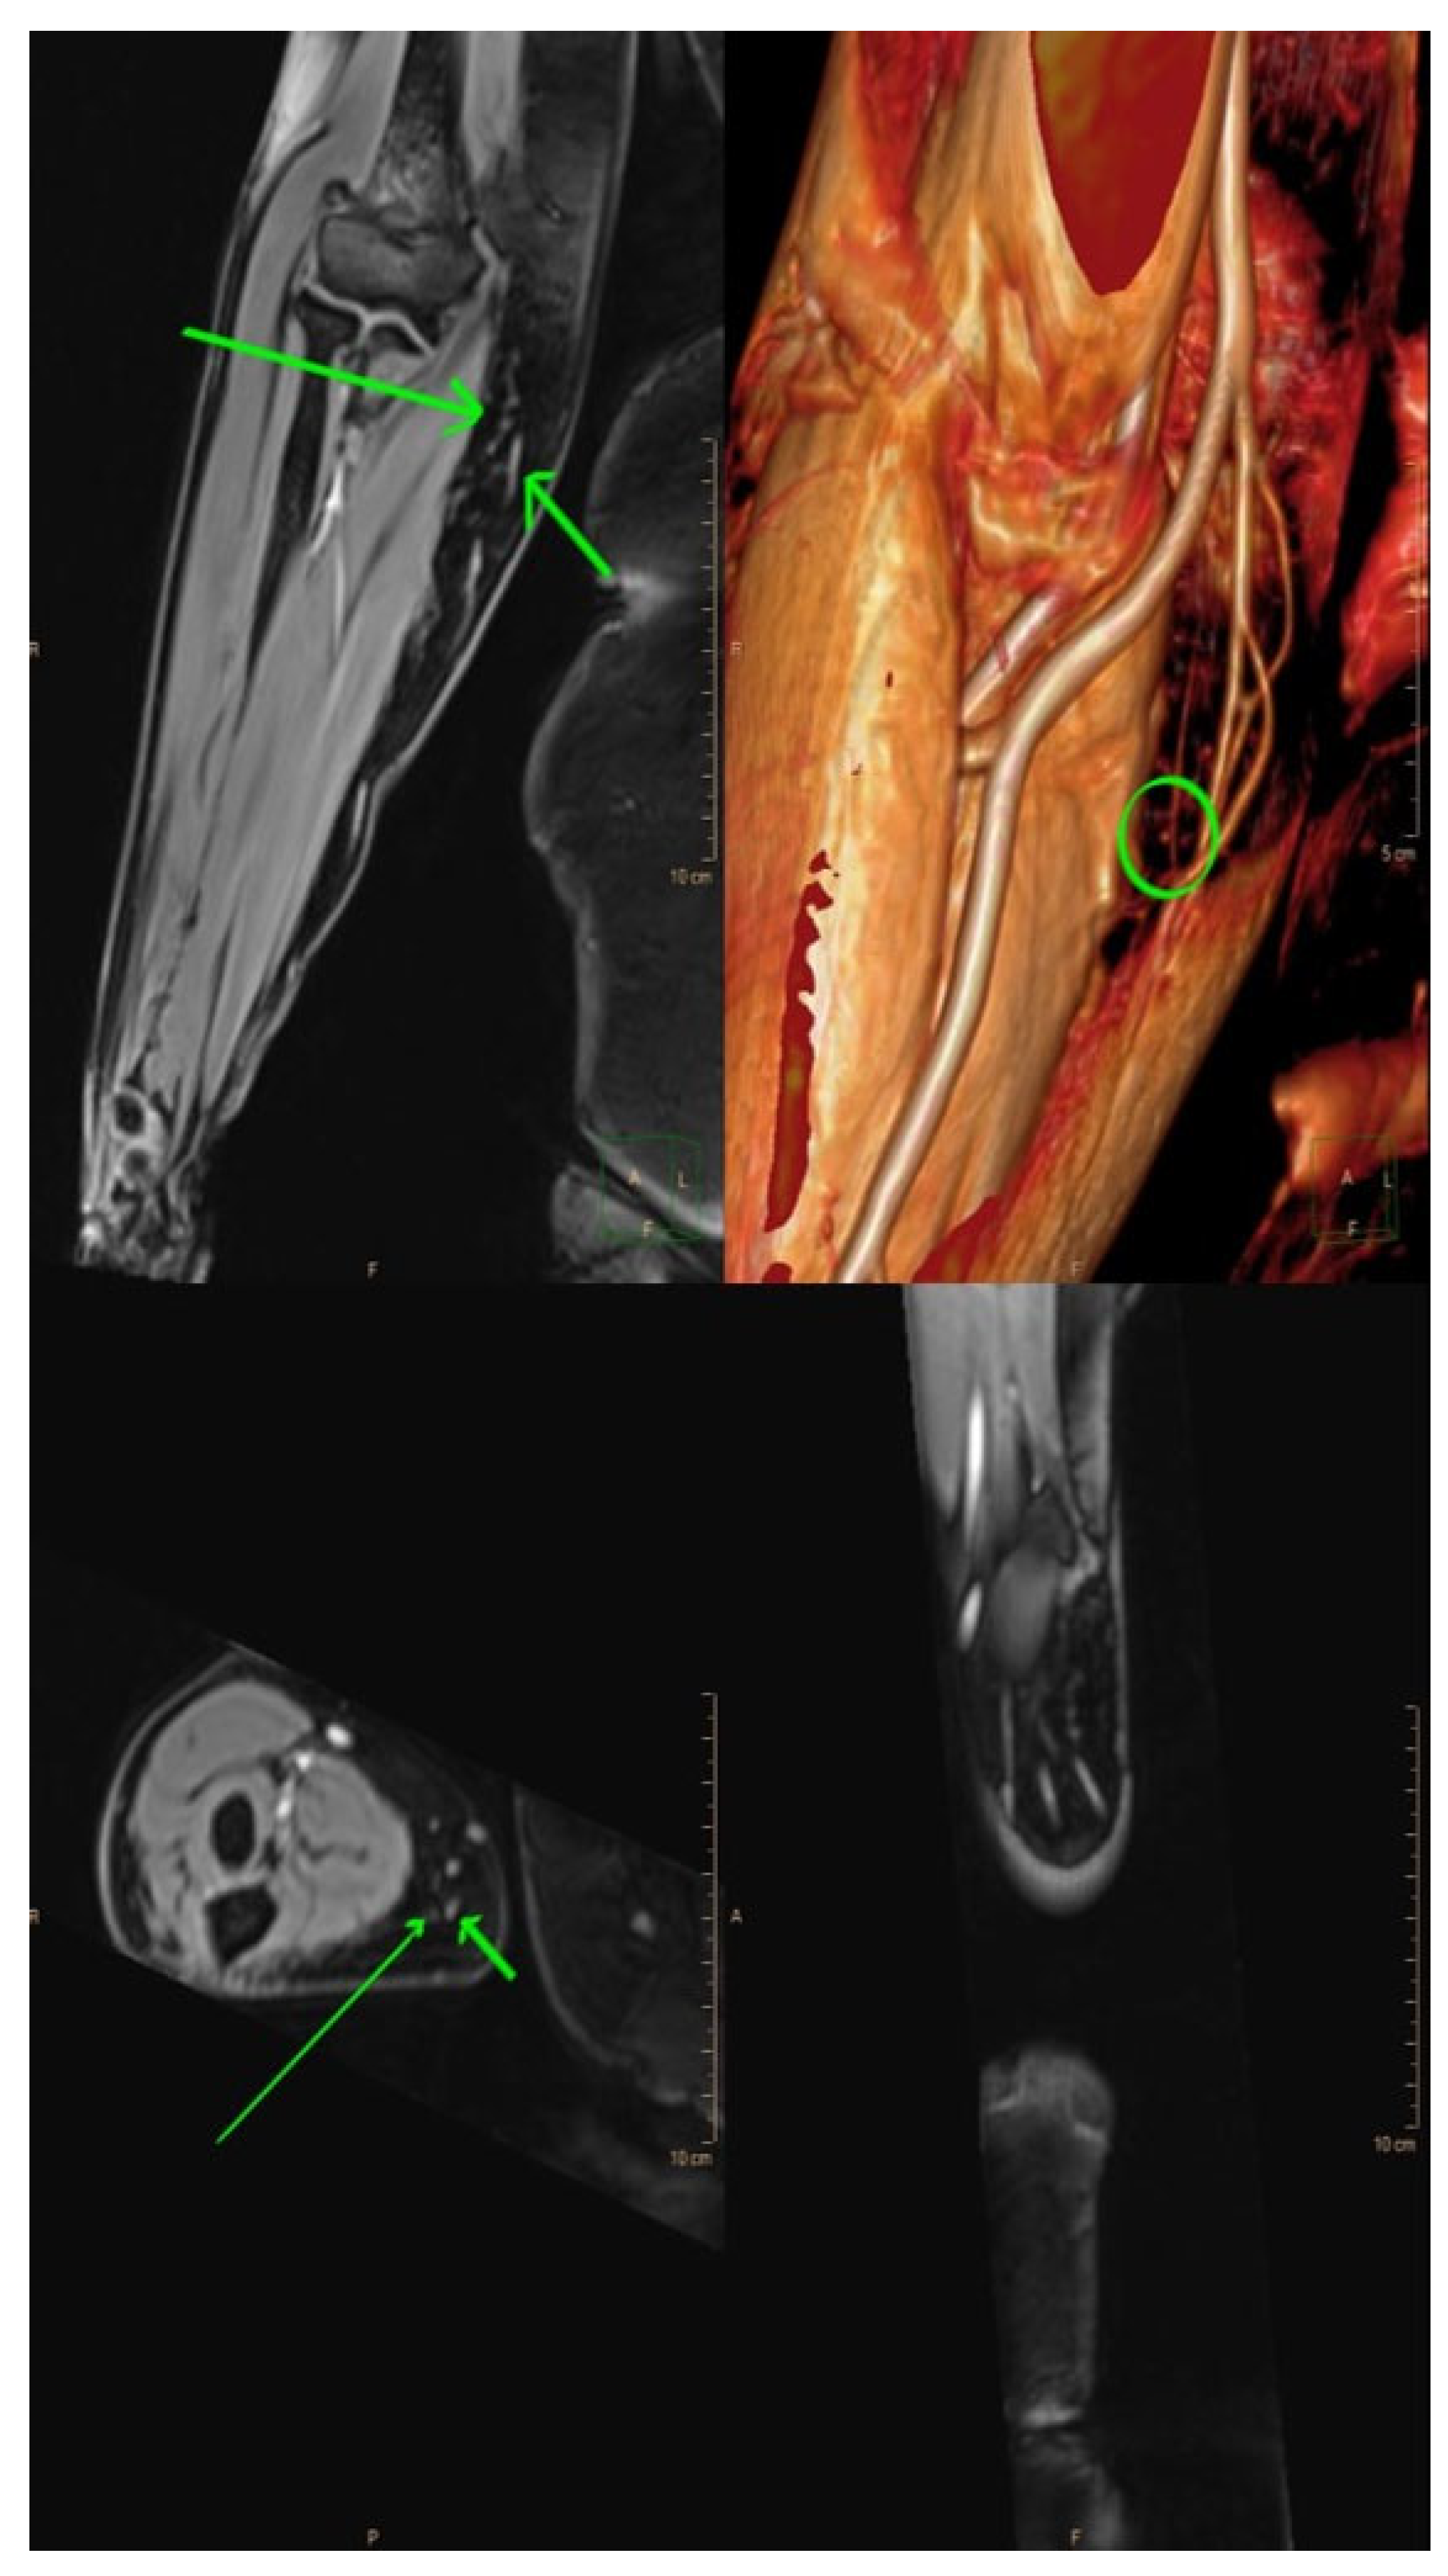

Figure 3.

Magnetic resonance lymphangiography provides anatomic delineation and 3D reconstruction images of lymphatics and adjacent veins. Long arrows = lymphatic channels; short arrows = vein; and circle = the crossing of both (the possible place of incision).

Magnetic resonance lymphangiography (MRL) is typically performed by intradermally injecting a gadolinium-based contrast agent in the interdigital web spaces. There is also a possibility of performing MRL without the injection of a contrast agent, but no information is obtained about the functional status of the lymphatics and veins, and it has a lesser spatial resolution when compared to contrast-enhanced MRL [12]. Contrast-enhanced MRL produces high-resolution images of the lymphatic channels, including the number, size, depth, trajectory, and regions of dermal backflow [9]. In fact, MRL has a higher sensitivity to detect lymphatic vessel abnormalities than other imaging modalities such as lymphoscintigraphy (LSG), indocyanine green lymphangiography (ICG-L), and Ultrasound Doppler [9]. As opposed to ICG-L, MRL provides a three-dimensional image of the entire extremity and provides information about the quantity and quality of both the superficial and deep lymphatic systems. It also allows for the visualization of the lymph node basin, the venous system, and the quality of the interstitial fluid [1,2]. This capacity to identify and map functional lymphatic channels preoperatively makes MRL useful in determining suitable targets for performing lymphovenous anastomosis (LVA) (Figure 3). Studies [9,13] found that the concordant use of MRL and ICG-L in identifying functional lymphatic vessels correlates with a higher probability of successful LVA. Additionally, MRL can evaluate the composition of a lymphedematous limb, aiding in the determination of appropriate surgical treatment. Patients with normal subcutaneous tissues or fluid-dominant edema may benefit from microsurgical reconstruction, while adipose-dominant edema is usually treated with liposuction, and fibrosclerotic-dominant edema is treated with direct excision [1]. A study performed by Dayan et al. [14] found that even patients within the same International Society of Lymphology class may have different percentages of fat and fluid, which can impact the treatment choice, and demands an appropriate preoperative assessment. However, MRL is an expensive tool compared to ICG-L, it may produce images with venous enhancement due to venous uptake of the contrast agent, it is time-consuming, difficult for patients with claustrophobia, and might be impossible for patients with non-compatible implants [15].